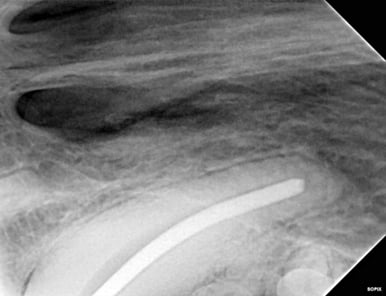

Below: After cleaning, a gutta-percha point was sized to aid in filling, with radiographic confirmation of reaching the tip.

%20-%20March%202024/Radiograph%20of%20dry%20fit%20of%20gutta%20percha%20during%20RCT.jpg?width=386&height=297&name=Radiograph%20of%20dry%20fit%20of%20gutta%20percha%20during%20RCT.jpg)

The test size was then removed, and the canal was filled with a liquid version of gutta percha, pressing in the solid gutta-percha point to the working length. Excess gutta-percha was trimmed and the walls cleaned using special techniques.

Below: After RCT - final mid root fill of solid and liquid turned solid gutta percha.

%20-%20March%202024/Radiograph%20of%20final%20fill%20of%20RCT%20-%20middle.jpg?width=386&height=297&name=Radiograph%20of%20final%20fill%20of%20RCT%20-%20middle.jpg)